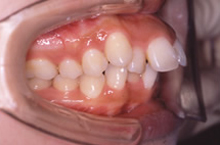

| 症状 | 前歯が出っ張ってものが噛み切れません。 歯並びの幅が狭くなり,下顎が後ろに押されています。 |

歯を抜いても歯並びが狭く小さくならないように治療します。

歯並びの幅が広がって、きれいなU字型になってきました。これが本来の歯列の形です。